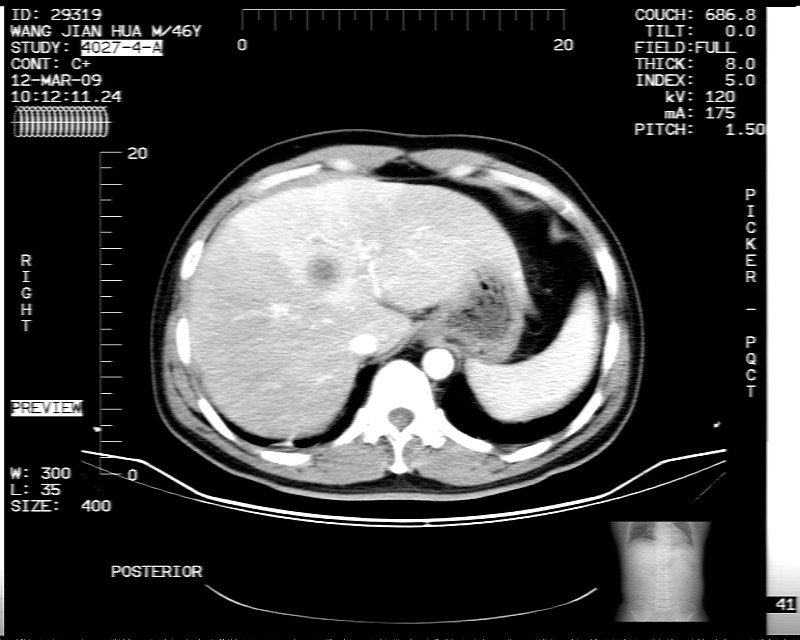

男性,52岁,腹痛,无发热,生化检查无明显异常,既往有胰腺炎病史,经治疗好转出院。

胆囊炎,肝脓肿(周围可见异常灌注)

1)考虑肝左叶内侧段肝脓肿,不排除转移瘤。2)脂肪肝。3)慢性胆囊炎。4)十二指肠降部肿瘤可能。

胆囊炎、脂肪肝、肝脓肿。